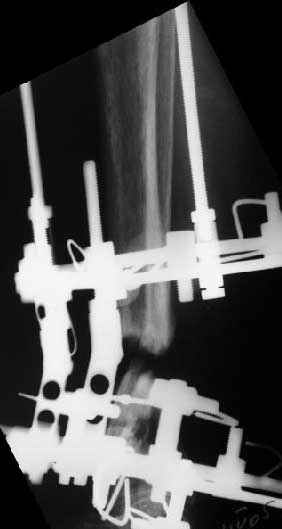

Аппарат - чтобы плавно исправить ось. В приложении - снимки на момент окончания коррекции в аппарате, фото с операции, и послеоперационная рентгенограмма.

Диаметр гвоздика 10,5 мм. Пришлось укорачивать до 23 см - уж очень миниатюрная дама, отверстия насверлил под 45 градусов, под 5 мм винты. По оси удалось сблизить до этого положения. Заперли гвоздь пока статически с планом через 2 месяца верхний винт убрать. Но это ей придется уже в Ташкенте сделать. Что скажете? Спасибо.

In attachment - x-rays at the end of alignment, the surgery, and result. The nail was cut to 23 cm. Four 45 degree holes were pre-drilled at the distal nail tip. The nail was locked statically

after some impaction. Dynamization is considered in 8 weeks. Any comments/critics?

> In attachment - x-rays at the end of alignment, the surgery, and

> result. The nail was cut to 23 cm. Four 45 degree holes were

> pre-drilled at the distal nail tip. The nail was locked statically

> after some impaction.

Amazing! How can you find the pathway of the nail through all those wires and the distal screws through so much hardware?